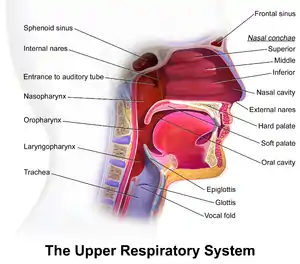

Upper respiratory system, with soft palate labeled near center. | |

The soft palate is moveable, consisting of muscle fibers sheathed in mucous membrane. It is responsible for closing off the nasal passages during the act of swallowing, and also for closing off the airway. During sneezing, it protects the nasal passage by diverting a portion of the excreted substance to the mouth.

A speech sound made with the middle part of the tongue (dorsum) touching the soft palate is known as a velar consonant.

It is possible for the soft palate to retract and elevate during speech to separate the oral cavity (mouth) from the nasal cavity in order to produce the oral speech sounds. If this separation is incomplete, air escapes through the nose, causing speech to be perceived as nasal.